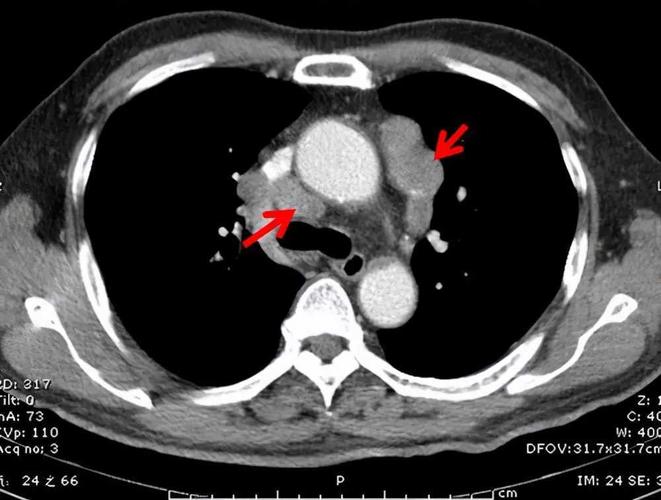

纵隔淋巴结肿大ct图解

纵隔淋巴结肿大ct图像

纵隔淋巴结ct片图解